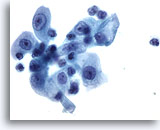

Miction, atypie

En présence de groupes de cellules, un échantillon peut être classé dans la catégorie “atypie”. Ces échantillons sont normaux dans environ 20 % des cas.

60x

Miction, atypie

En présence de groupes de cellules, un échantillon peut être classé dans la catégorie “atypie”. Ces échantillons sont normaux dans environ 20 % des cas.

60x